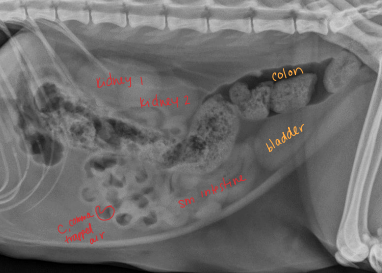

Large Intestine Surgical Considerations

Three segments: ascending, transverse, descending (longest part) left side

Cecum

Dt: rectal exam, contrast rads, US

Surgical Conciderations of the Bladder

Healing: regains 100% strength in 14-21d, full re-epithelialization in 30d, 50% can be removed safely

avoid incisions near trigone